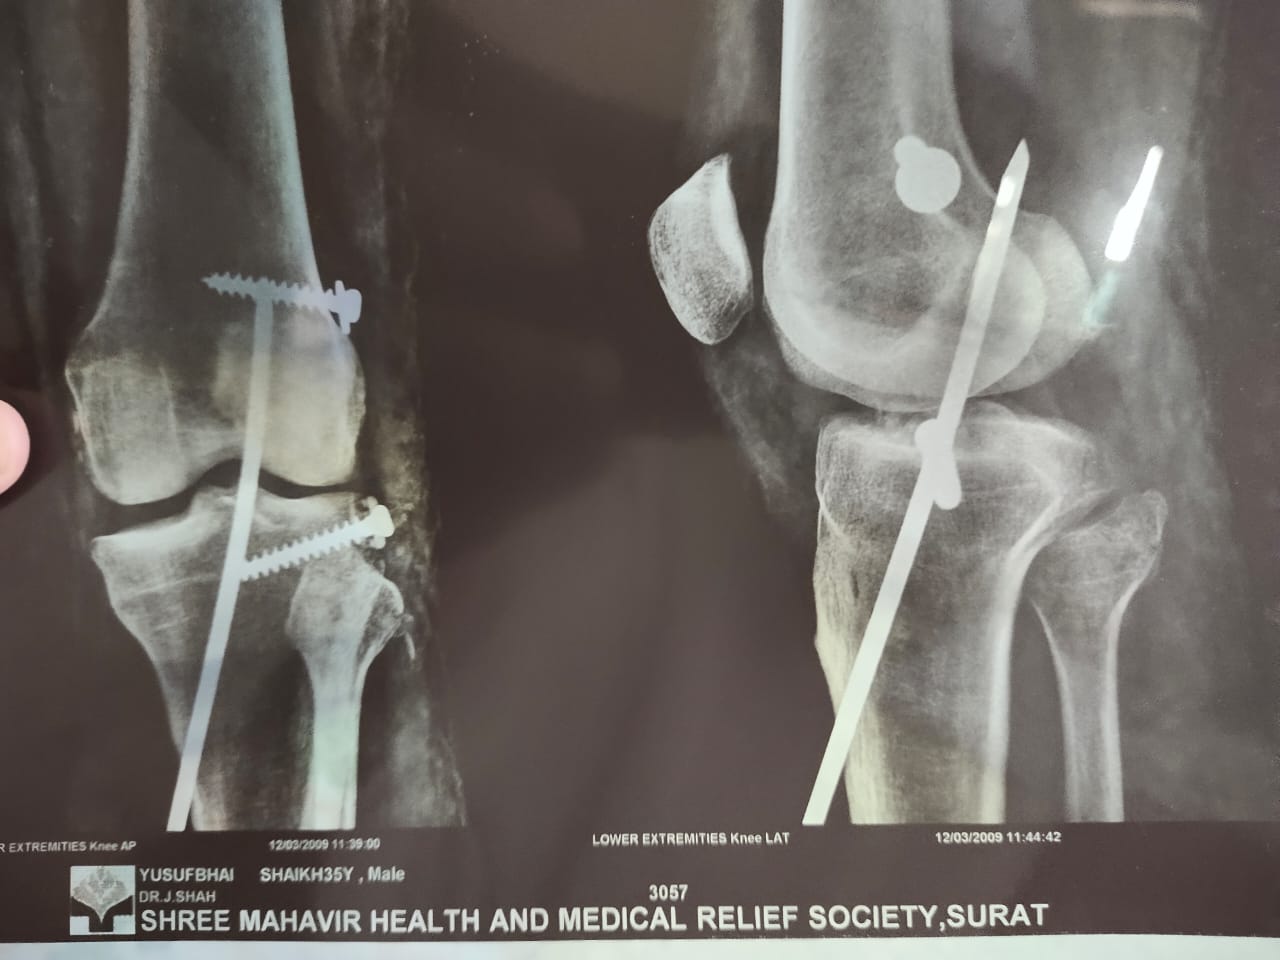

हमने इलियास से इस पूरी घटना के बारे में जानने के लिए कॉन्टैक्ट किया. उन्होंने बताया, “मैं डाभेल जाने के लिए 22 तारीख की सुबह निकला था और मैंने रास्ते में पड़ने वाले इस पेट्रोल पम्प पर पेट्रोल भरवाया. हाईवे पर गाड़ी चला रहा था तो इसी वजह से मैंने चश्मे और मास्क पहने थे. मेरा 2009 में एक एक्सीडेंट हुआ था जिसकी वजह से मैं अपने दाहिने हाथ से कुछ ठीक से पकड़ नहीं सकता हूं. मेरा ये हाथ हरकत तो करता है लेकिन उससे मैं कोई भी चीज़ पकड़ नहीं सकता. इसी वजह से मेरे दाहिने हाथ से कब नोट गिर गई मुझे पता नहीं चला. आपने अगर वीडियो देखा है तो आपको मालूम होगा कि मैंने अपने उलटे हाथ से जेब से पैसे निकाले और उन्हें दिए. इसी बीच मेरे अंगूठे में एक नोट फंस गई जिसका मुझे पता ही नहीं चला और वो नोट मेरे हाथ से गिर गई.”

इलियास से FIR के बारे में पूछने पर उन्होंने बताया, “मुझे वलसाड पुलिस स्टेशन में बुलाया गया था और पूछताछ की गई थी. तब मैंने उन्हें बताया कि मैं नवसारी नहीं गया था लेकिन हाईवे के रास्ते से मैं डाभेल ज़रूर गया था. मेरे कंधे के नीचे स्टील का रॉड डाला गया था जिसकी वजह से कभी-कभी मुझे दर्द होता रहता है और मुझे हर 2-3 महीने में डॉक्टर के पास चेक-अप करवाने के लिए जाना पड़ता है. उसके बाद वहां पर नवसारी पुलिस स्टेशन से कुछ लोग आए और मुझे नवसारी के रूरल पुलिस स्टेशन ले गए. वहां पर नवसारी के सरकारी हॉस्पिटल में ले जाकर मेरा चेक-अप करवाया गया. इसके बाद डॉक्टर ने साफ़ कर दिया कि मुझे कोई प्रॉब्लम नहीं है और कोरोना के कोई भी लक्षण नहीं हैं. मुझे तब तक इस मामले के बारे में कुछ मालूम ही नहीं था. उसके बाद मैंने अपने पैरालिसिस हो चुके हाथ के बारे में पुलिस को बताया तो उन्होंने भी माना कि मैंने जान-बूझकर नोट नहीं फेंका था. इसके बाद पेट्रोल पम्प के लोग भी वहां पर आए और उन्होंने मेरा हाथ देखा. सभी ने ये बात मान ली कि मेरे हाथ से नोट गलती से गिर गई थी. इसके बाद मुझे ज़मानत दे दी गई. मुझे डॉक्टर ने घर पर ही रहने के लिए कहा है और इसीलिए मैं अपने घर पर ही रहता हूं.” इलियास ने इस पूरी घटना के बारे में एक वीडियो रिकार्ड कर हमें भेजा है जिसमें आप उनके घायल हाथ को साफ़ देख सकते है.

इलियास के एक्सीडेंट के बाद उनके हाथों और कन्धों का एक्स-रे यहां देखा जा सकता है.